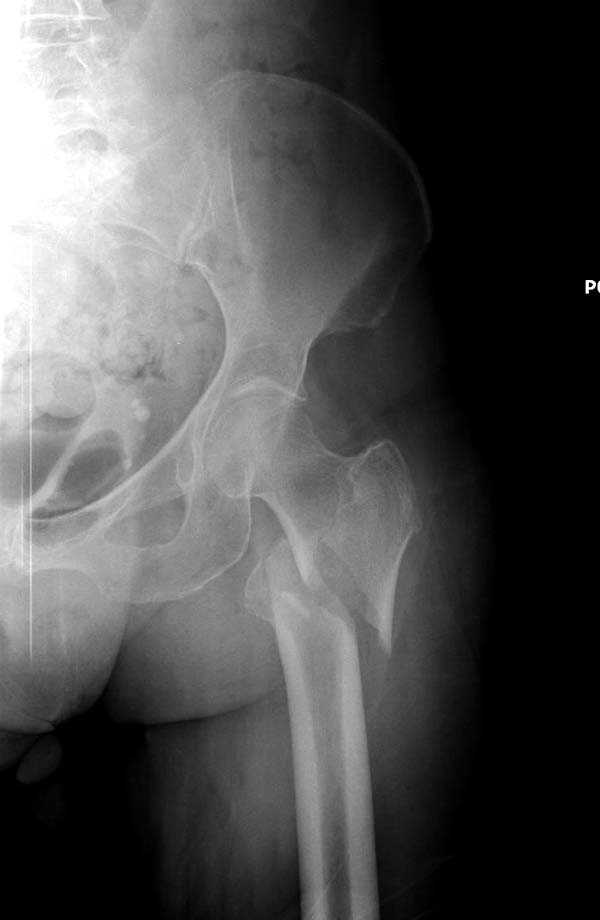

Для лечения переломов проксимального бедра существует различные конструкции, включая цефаломедуллярные. Среди них из-за простоты и удобной конструкции распространенным является Gamma.

Здесь представлен случай, где в послеоперационном периоде обнаружена техническая ошибка, Gamma 3 установлен с нарушением методики. Больная в 91 лет, прооперирована через день после поступления и выписана через 48 часов.

При первом послеоперационном поликлиническом осмотре больная предъявила жалобы на боли в бедре. В серийных снимках обнаружен продольный перелом верхнего отдела бедра.

Считаем, что техническая ошибка произошла во время установки гвоздя, когда рассверливанию канала не уделили должного внимания. Канал остался узковат, и гвоздь был забит с силой. Полная нагрузка конечности приостановлена на две недели, и боли в конечности изчезли. Больная начала нагрузку и перелом срастается.-- Djoldas Kuldjanov, M.D.Associate ProfessorDepartment of Orthopedic SurgerySt. Louis University